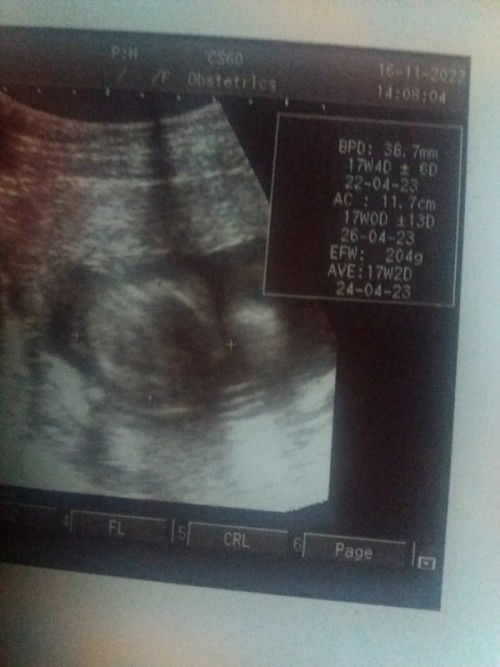

#ingintahu Mau tanya dong , Dsni ada gk yg usia hamil nya 17week , blm ngerasain gerakan2 gtu,sama perut kaya masih datar gtu . Pdhal sy anak ke 2 , tapi kok diri syaa sendiri kaya merasa kok ini perut kecil yah , Jangan di Bully yah . Tinggi saya 160 ,BB 54 , atau krena sya tinggi atau gimana yah . Gak salah kok kalau kita dsni saling berbagi cerita .